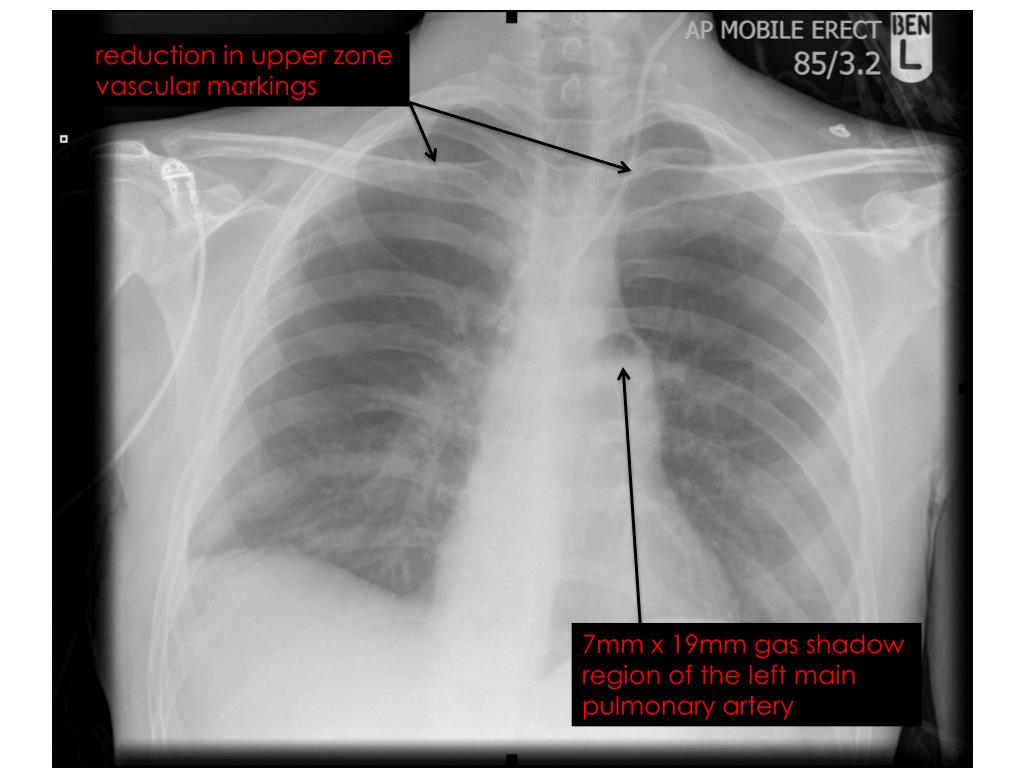

7. Venous Air Embolism (VAE) Suspected • left lateral decubitus position • distal lumen of CVC aspirated • No further air withdrawn • AP mobile erect CXR taken to aid diagnosis

8. reduction in upper zone vascular markings 7mm x 19mm gas shadow region of the left main pulmonary artery

9. Supportive Management • sat up as most comfortable • 100% oxygen • gradual improvement over 30 minutes • discharged at 90 minutes • oxygen • level 2 care • follow up revealed no persistent problems